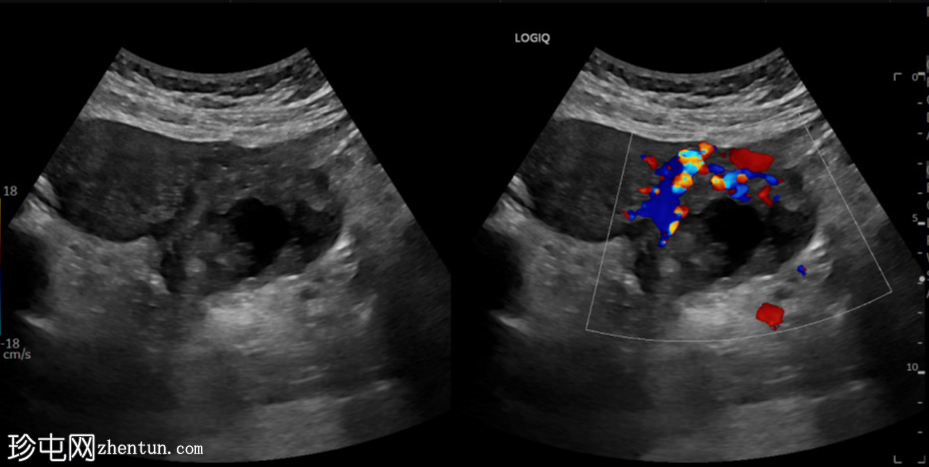

纵切面

左侧卵巢明显增大,可见一囊肿,大小约3.2 x 2.3 cm,呈火环征,可能为黄体囊肿。左侧卵巢与子宫之间可见一管状结构,直径约1.3 cm,内含浑浊液体,未见血管,最可能为输卵管积血。以上特征提示可能为左侧异位妊娠。

未见宫内妊娠囊。